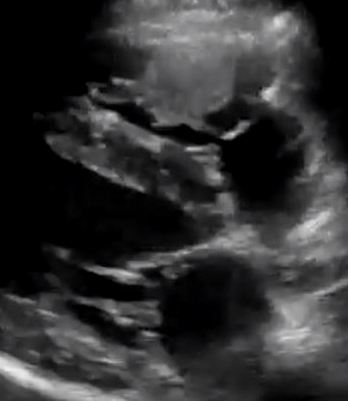

Sonographic features of cardiac hepatopathy in a dog with cor triatriatum dexter

I have to confess that this dog caught me out initially. A 12 m.o. Springer Spaniel; relatively well in herself but presenting with abdominal distention due to progressive ascites (of the modified transudate variety). No loud murmur. This is the liver: That’s not normal. The parenchyma is heterogeneous: specifically, the centres … Continue reading